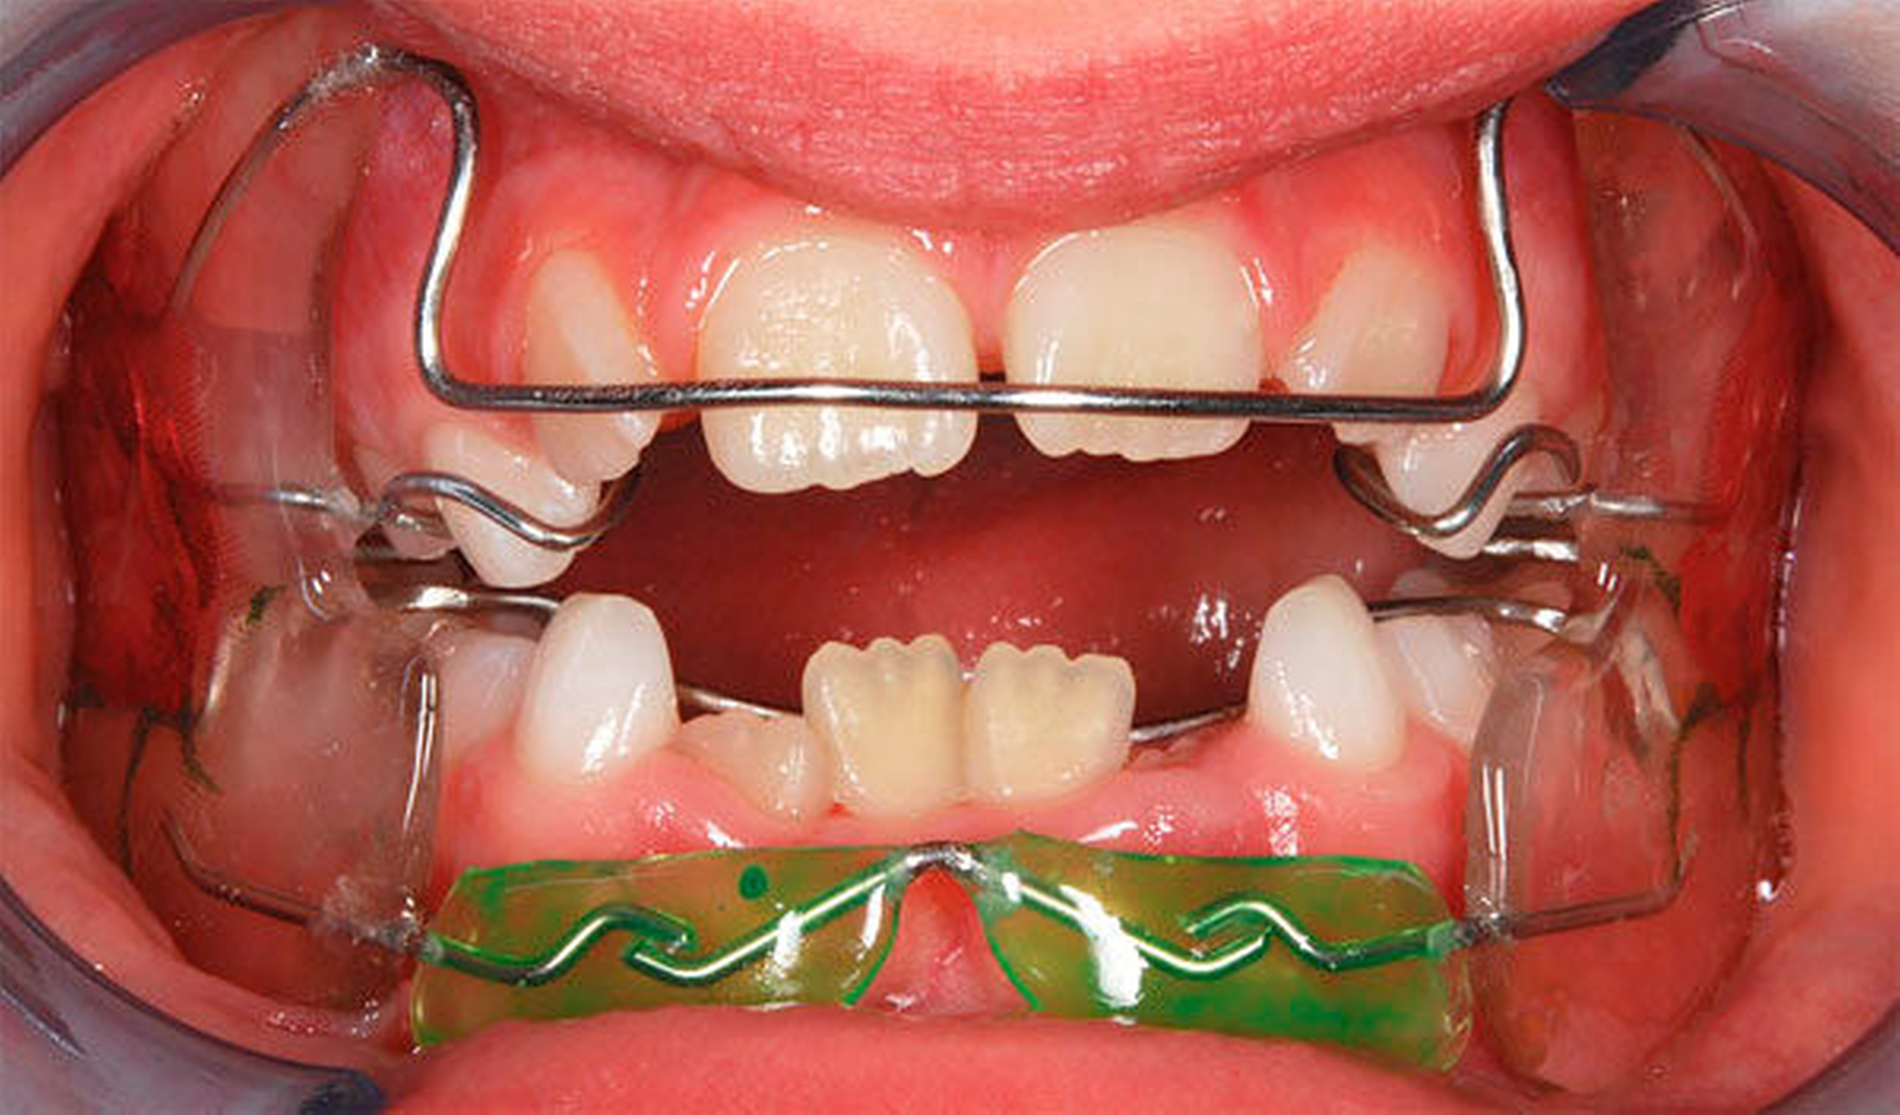

In der Gruppe des progenen Formenkreises werden Zahn- und Kieferfehlstellungen unterschiedlichster Ätiologie zusammengefasst. Diese können durch ein Missverhältnis im Wachstum beider Kiefer bedingt sein, das heißt durch Überentwicklung (Makro-/Prognathie) des Unterkiefers und/oder Unterentwicklung (Mikro-/Retrognathie) des Oberkiefers [Rakosi, 1989]. Besteht ein frontaler Kreuzbiss von Einzelzähnen oder einer ganzen Zahngruppe wird der Oberkiefer durch den Unterkiefer „eingefangen“, das heißt durch die palatinalwärts positionierten OK-Inzisiven wird das Oberkieferwachstum im Alveolarfortsatzbereich gehemmt sowie das Unterkieferwachstum „freigegeben“, da der Unterkiefer sich postnatal in sagittaler Richtung ohnehin stärker als der Oberkiefer entwickelt [Lux, 2004]. Zudem kann eine Zwangsbissführung des Unterkiefers nach ventral vorliegen [Keeling, 1998]. Diese kann zusätzlich zu einer unerwünschten Wachstumsstimulation des Unterkiefers mit nachfolgender skelettaler Manifestation führen. Mit einem therapeutisch eingestellten sicheren frontalen Überbiss (sagittal und vertikal) kann die weitere Kieferentwicklung koordinierter ablaufen (Abbildung 4). Die Anomalien des progenen Formenkreises besitzen häufig auch eine hereditäre Komponente, wobei unphysiologische Ruheweichteilbeziehungen oder Dysfunktionen den Phänotyp deutlich verstärken können. Da bei Klasse-III-Dysgnathien die skelettalen Therapieergebnisse bei frühzeitigem Behandlungsbeginn am besten sind, sollte frühzeitig mit einer kausalen Therapie begonnen werden – also sobald eine ausreichende Compliance des Patienten es zulässt, [Baccetti, 1998; Da Silva, 1998; Franci, 2004; Lang, 2001; Saadi, 2000].